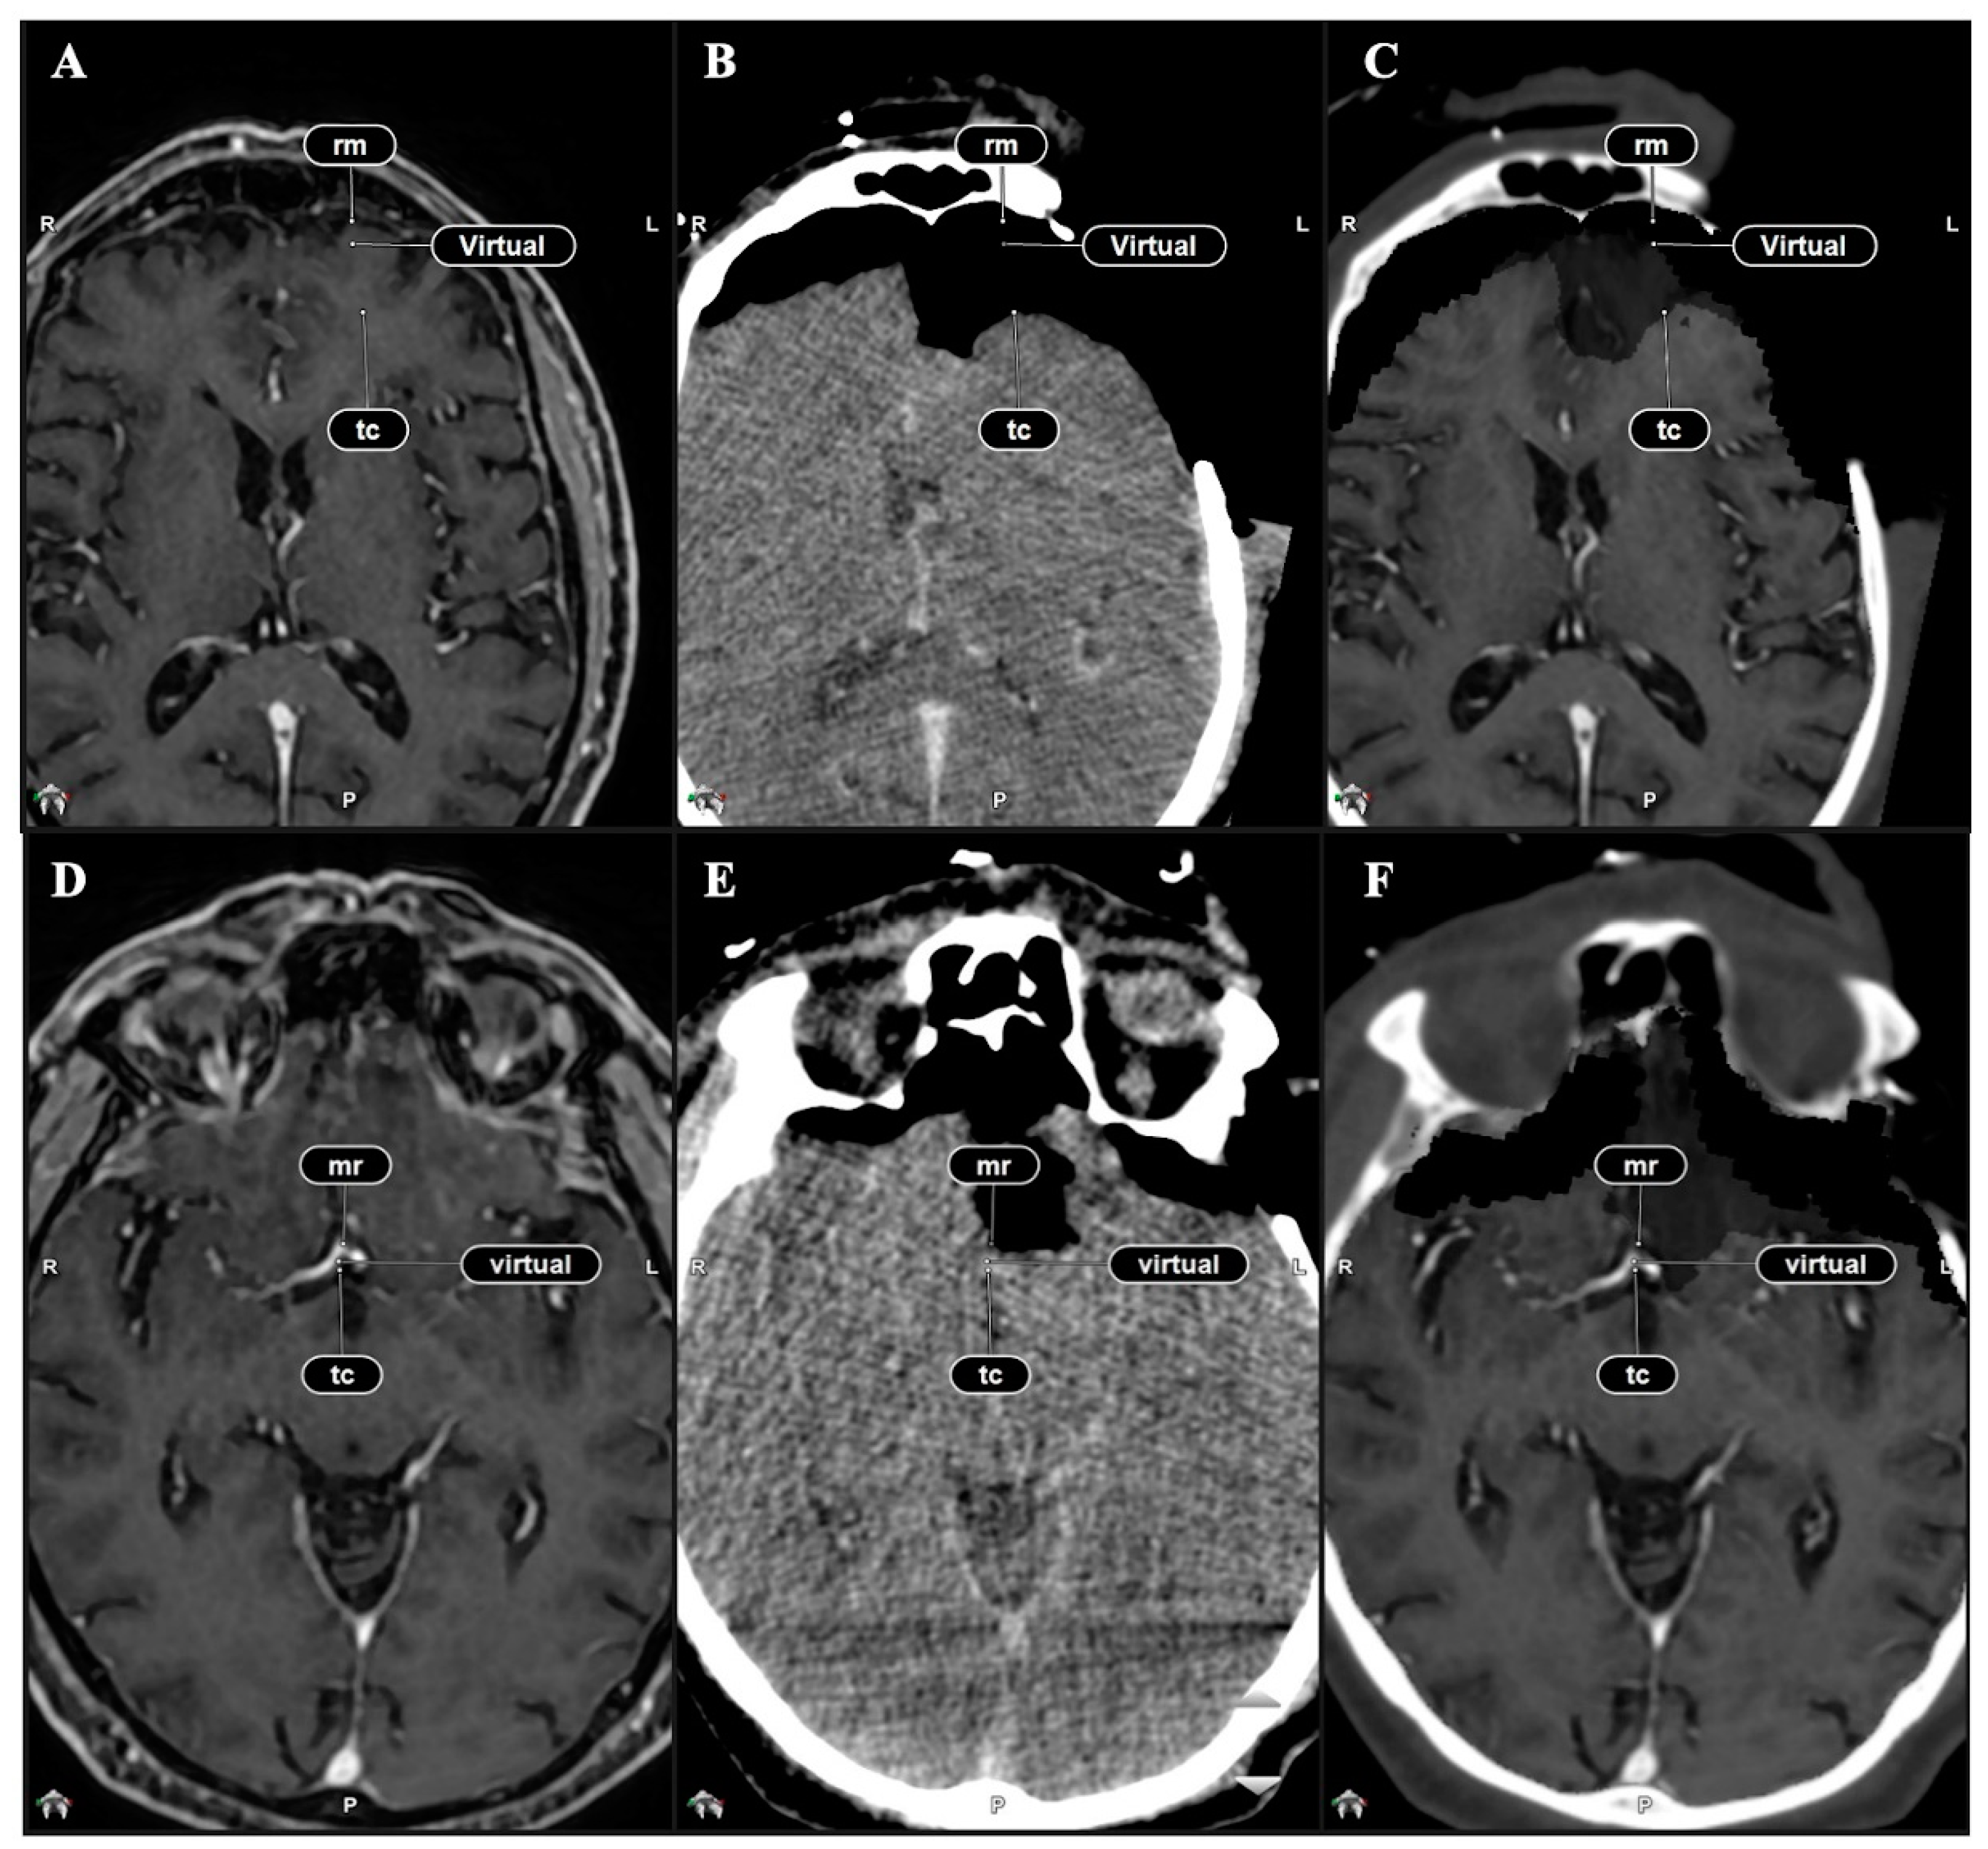

2.5. Qualitative Comparison of iCT, Virtual iMRI, and Post-Operative MRI

3.2. Analysis on Accuracy: Quantitation of the Target Registration Error

3.3. Qualitative Evaluation